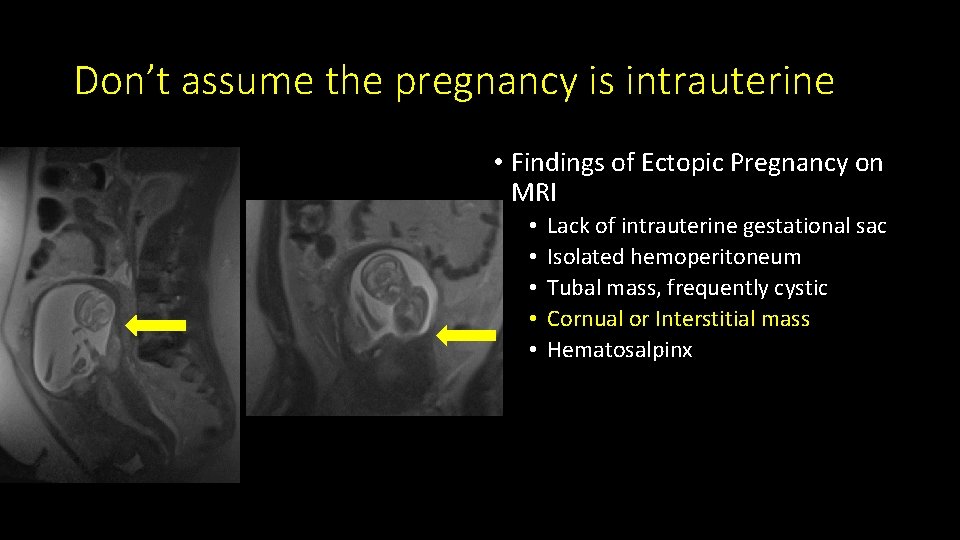

Don’t assume the pregnancy is intrauterine • Findings of Ectopic Pregnancy on MRI • • • Lack of intrauterine gestational sac Isolated hemoperitoneum Tubal mass, frequently cystic Cornual or Interstitial mass Hematosalpinx

Don’t assume the pregnancy is intrauterine • Findings of Ectopic Pregnancy on MRI • • • Lack of intrauterine gestational sac Isolated hemoperitoneum Tubal mass, frequently cystic Cornual or Interstitial mass Hematosalpinx

Don’t assume the pregnancy is intrauterine • Findings of Ectopic Pregnancy on MRI • • • Lack of intrauterine gestational sac Isolated hemoperitoneum Tubal mass, frequently cystic Cornual or Interstitial mass Hematosalpinx

Don’t assume the pregnancy is intrauterine • Findings of Ectopic Pregnancy on MRI • • • Lack of intrauterine gestational sac Isolated hemoperitoneum Tubal mass, frequently cystic Cornual or Interstitial mass Hematosalpinx